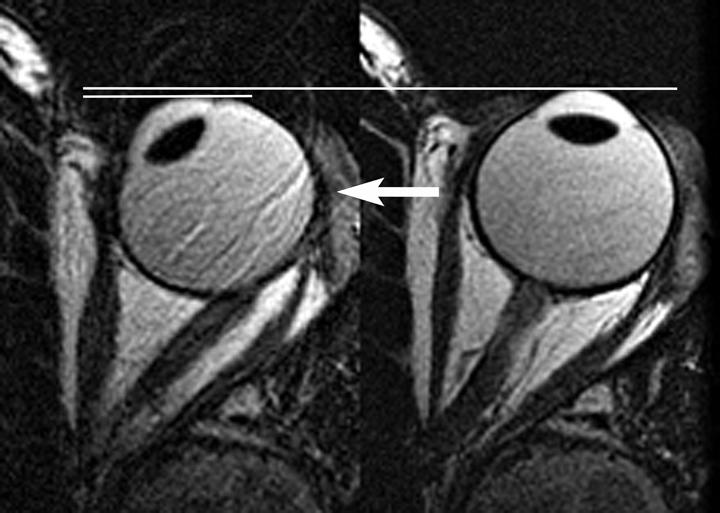

Magnetic resonance imaging (MRI) scans show the optic nerve acting as a tether, resisting eye rotation from central gaze (right) towards the nose (left), and causing the eyeball to retract (horizontal lines) when the eye rotates further into the tether effect. The black oval inside the eye is the lens at the front of the eye.

The results, published in Investigative Ophthalmology and Visual Science, show that for both groups the optic nerve and its surrounding sheath act as a kind of tether on the eyeball.

1 For everyone, the tether was slack in abduction and taut in adduction. In the group with normal-tension glaucoma, however, the tethering in adduction caused the globe to retract significantly. This suggests that in people with normal-tension glaucoma, the optic nerve and the sheath are strained in adduction, which in turn mechanically loads the globe of the eye against the forces of the medial rectus, the muscle that controls horizonal eye movement. By contrast, the optic nerve and sheath in healthy study participants stretched freely, absorbing the strain of adduction on the eye’s tissues.